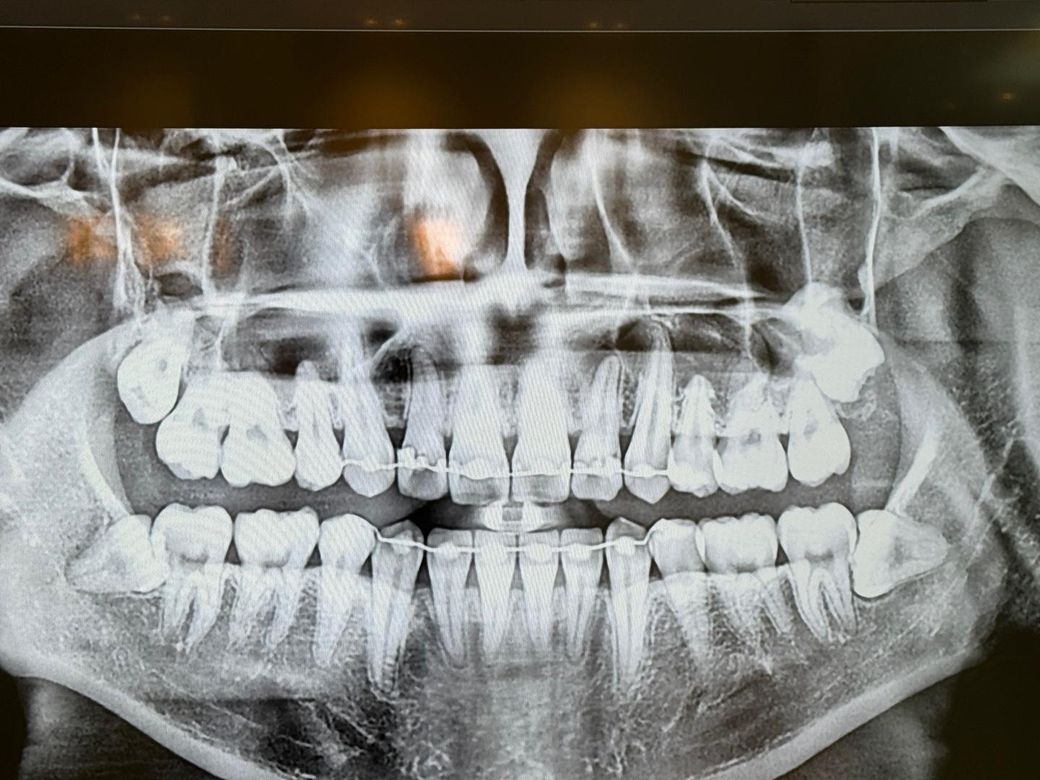

• 1번 째 사진

엑스레이 상으로는 치아 뿌리끝 염증이 더 확장된거 같습니다. 신경치료를 하시는게 좋을것같습니다.